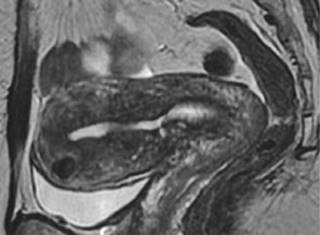

Para el uso de ultrasonido se recomienda un abordaje transvaginal, encontrando infiltración endometrial: con estriaciones ecogénicas y nódulos, quistes miometriales y divertículos “lollipop”; así como proliferación de músculo suave, ya sea de tipo focal o difuso con bordes en el miometrio. En cuanto a la vascularidad, mediante ultrasonido Doppler se observa aumento de la angiogénesis con vasos tortuosos. La mayor sensibilidad en el diagnóstico se logra con el uso de la resonancia magnética, en la que los hallazgos son similares a los observados en el ultrasonido;8 dentro de estas observaciones se entiende lo siguiente:9 en las imágenes T2 se observa alargamiento uterino con regiones más definidas y de baja intensidad con hiperplasia del músculo liso (zona de unión de más de 12 mm), quistes miometriales hiperintensos que reflejan regiones del tejido miometrial ectópico; con posible señal T1 intrínseca incrementada o con mayor sensibilidad para focos hemorrágicos. No existe recomendación de mejora con el medio de contraste, ya que no permite valorar o identificar la vascularización de la zona (Figura 2).

Figura 2: Ultrasonido endovaginal corte sagital que muestra imágenes quísticas y anecoicas de tamaño variable distribuidas en el miometrio.